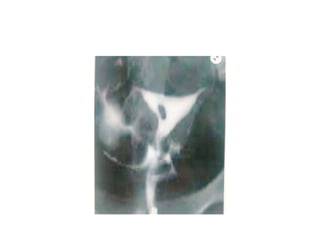

SEPTATE UTERUS

• Intercornual angle- <75

• Intercornual distance <2cm

BICORNUATE UTERUS

• Intercornual angle ->105

• Intercornual distance 2-4cm

SEPTATE UTERUS • Intercornualangle- <75 • Intercornual distance <2cm BICORNUATE UTERUS • Intercornual angle ->105 • Intercornual distance 2-4cm